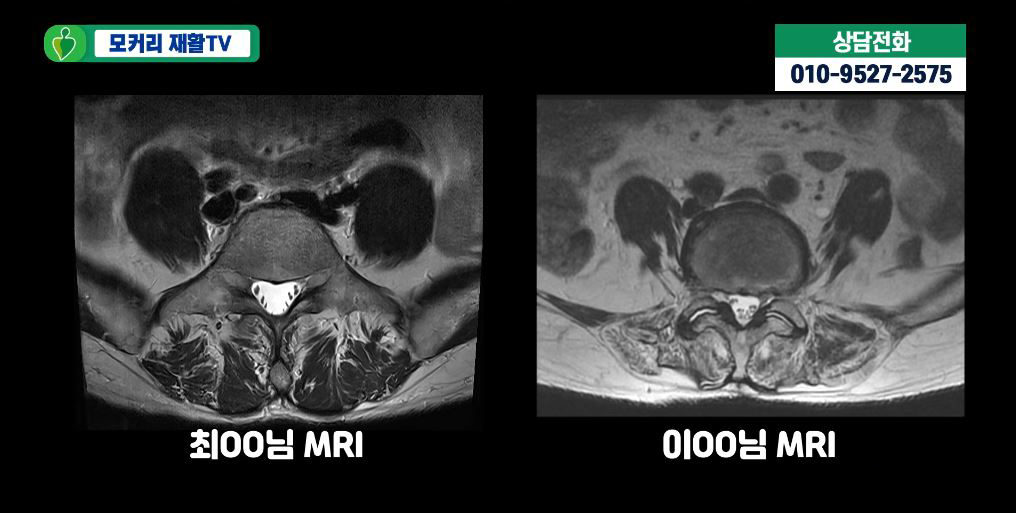

아래 사진은 실제 근감소증 환자들의 MRI입니다.

이 환자분들의 MRI를 보면 두분 다 60세 이상이시라 노화로 인해 MRI상으로 협착과 퇴행성디스크가 보입니다.

하지만 협착이 심하지 않아서 다리로 가는 신경을 누르는 것 같지는 않습니다. 이분들의 엉덩이나 다리증상이 협착증 증상이 아닐 가능성이 높은 것입니다. 그럼에도 불구하고 이분들처럼 MRI로 퇴행성디스크와 협착이 보이고 허리와 다리가 아프면 무조건 협착증이라고 진단하는 경우가 매우 많습니다. 이분들도 역시 협착과 퇴행성디스크 진단을 받았습니다. 하지만 이분들의 허리통증, 엉덩이통증, 다리증상과 걷는 게 힘든 증상은 협착과 퇴행성디스크 문제보다는 근감소증과 근육 뭉침 때문입니다.

보시다시피 두분 다 척추기립근도 지방화가 심하게 돼있고, 근감소증 검사에서도 양성반응을 보이셨습니다. 이렇듯 협착증이 아닌데 협착증으로 잘못 진단하게 되면 엉뚱한 치료를 받으면서 시간만 낭비하고, 또 고생은 고생대로 하면서 치료가 안 되는 그런 결과를 낳게 됩니다. 따라서 반드시 협착증과 근감소증을 잘 구별해야 하며, 최근에 유달리 근육이 많이 줄어들었고, 특히 허리가 아프고 구부러지며, 걸음걸이가 느려지면서 다리가 아픈 증상이 나타난다면 근감소증 검사를 받아볼 필요가 있습니다.